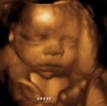

Встреча с малышом в 32 недели

И так наступила 32-я неделя и мы с мужем отправились на узи которого с нетерпением так долго ждали.

Теперь малыш стал совсем большим,его очень хорошо видно и абсолютно понятно, что это непросто эмбрион, а настоящий человек!!!

Потом доктор показала нам все органы будущего ребенка и заверила,что все в порядке, никаких патологий нет. Мы, естественно, удовлетворились услышанным.

Так интересно смотреть: все такое маленькое, крохотное, а уже полностью функционирует как у взрослого человека... А ведь он совсем еще кроха,которая даже на свет не появилась.

Но моего мужа больше всего волновало другое...Точно ли у него будет сын и не ошибся ли врач на предидущем узи в 22 недели. Он пять раз переспросил, тут узистка не вытерпила и ответила, что сейчас все ему покажет.